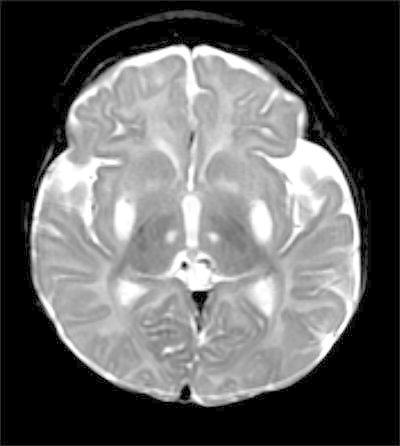

The patient had been doing well until 4 months of age, when he was noted to be losing weight by his primary care provider. He was admitted for an evaluation of failure to thrive and hypotonia. A brain MRI and an EEG were obtained for a concern for seizure-like activities. The EEG was initially normal. A brain MRI revealed abnormal signal and restricted diffusion in bilateral lenticular nuclei, the medial thalami and the caudate nuclei, as well as encephalomalacia (Figs. 1 and 2). An MR spectroscopy showed a lactate peak in the left anterior basal ganglia (Fig. 3). These findings were concerning for an underlying mitochondrial disorder, although a hypoxic-ischemic event was also a possibility. A muscle biopsy showed nonspecific changes in SDH, COX, and NADH stains. Electron transport chain enzyme spectrophotometry assay on snap frozen quadriceps muscle was unremarkable except for a reduced enzyme activity of the complex II (31% of mean). Respiratory chain complex V (ATP synthase) activity was not measured due to a technical limitation. A mitochondrial DNA mutation screening panel (leukocytes) was ordered due to the MRI findings and revealed homoplasmic m.8993T>G mutations in the MT-ATP6 gene encoding ATP synthase, leading to the diagnosis of Leigh syndrome. The mutant load was confirmed by real-time allele refractory mutation system (ARMS) quantitative PCR analysis. Mild persistent lactic acidosis with lactate levels in the range of 3–7 mol/L was consistent with the diagnosis. A therapy with coenzyme Q10 was started for the treatment of Leigh syndrome. l-citrulline was restarted at an increased dose of 1.1 g/day (200 mg/kg/day), as serum citrulline level had decreased to 5 μmol/L. An ophthalmologic eye exam revealed bull’s eye maculopathy consistent with the underlying diagnosis (Laird et al. 2006).

Fig. 1.

Axial T2. Abnormal increased signal in subganglionic tissues, lenticular nuclei, and medial thalamic nuclei